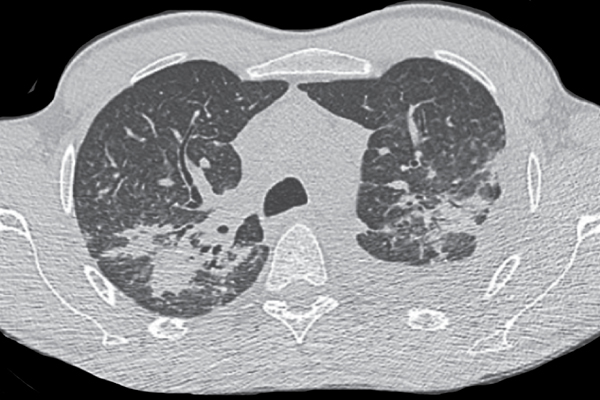

A 34-year-old man with untreated HIV-1 infection was admitted due to obstructive jaundice and progressive, nontender swelling in the left axillary region. The HIV vira...